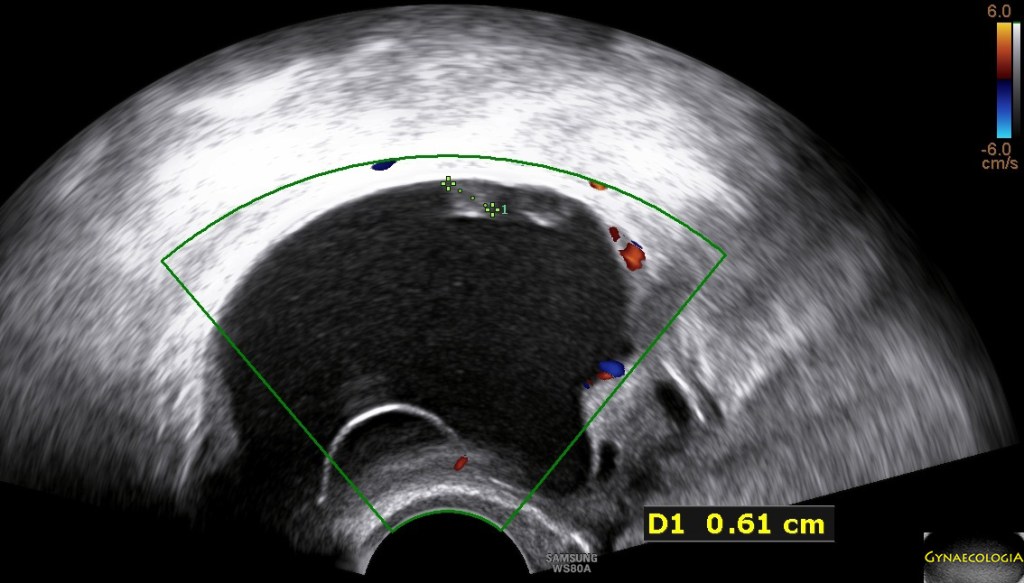

Ultrasound findings

- Frequently large, unilateral, cystic mass.

- Usually multilocular.

- Smooth walls.

- Contains small cystic components or honeycomb-like loculi.

- Intralocular fluid of varying echogenicity.

- Linear calcifications (rare).

- Papillary projections (rare).

- Mucinous ascites may present after cyst rupture.